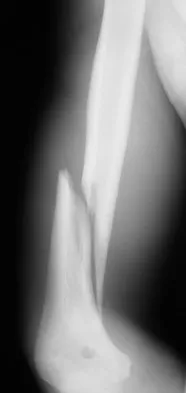

Question 16

A 15-year-old boy has a mass at the knee. Radiographs show an aggressive tumor involving the proximal tibia, and biopsy findings reveal a high-grade osteosarcoma. Staging studies show that the tumor impinges on the neurovascular bundle. The tumor enlarges during preoperative chemotherapy. Management should now consist of